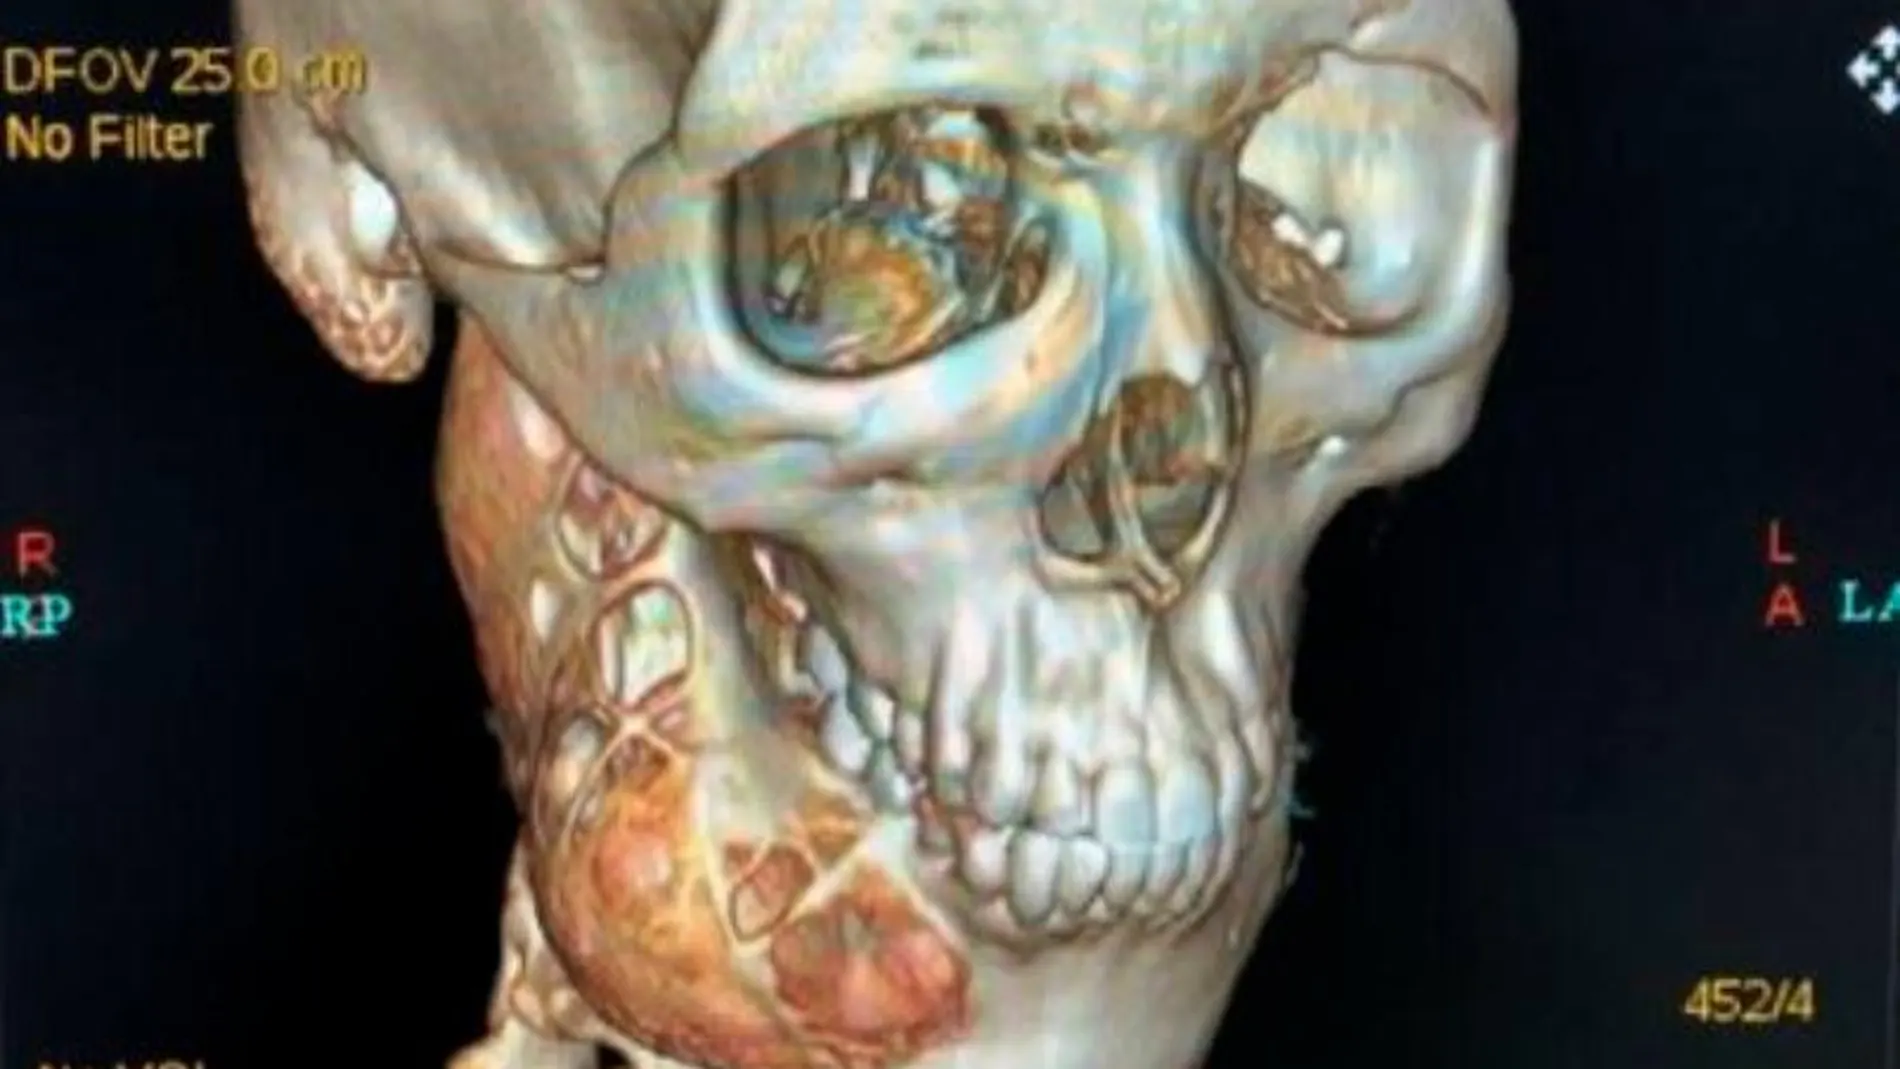

Increíble pero cierto. Un adolescente chino de 15 años soportó un dolor de muelas durante un año hasta que se hizo totalmente insoportable. Xiao Mo acudió al hospital de Hangzhou acompañado de su familia pensando que se trataba de una caries y se encontró con algo inesperado. Una tomografía 3D mostró que la lesión se había "comido"gran parte de la mandíbula y que tenía un "gran agujero"en el lado derecho. Los médicos confirmaron que tenía una amplia destrucción ósea junto con otras lesiones, según informan medios locales.

Pero ¿Qué pasó para que la mitad de los huesos de la cara se consumieran? Los médicos diagnosticaron que Xiao Mo tenía un tumor llamado ameloblastoma, que crece lentamente, pero tiene una gran invasividad local. Si no se elimina, la tasa de recurrencia es alta.

Para extirpar el tumor y recuperar la mandíbula dañada, los especialistas tuvieron que someterlo a cirugía. La reparación y reconstrucción de la mandíbula tienen gran dificultad ya que puede afectar a la correcta oclusión de los dientes. El paciente no puede comer y vivir normalmente después de la cirugía y la recuperación es lenta. Actualmente el adolescente se está recuperando y los médicos esperan que los implantes dentales lo ayuden a volver a comer con normalidad.

El ameloblastoma es un tumor no canceroso (benigno) poco frecuente que se desarrolla con mayor frecuencia en la mandíbula, cerca de los molares. El ameloblastoma comienza en las células que forman el revestimiento del esmalte protector de los dientes. Puede ser muy agresivo, extenderse hasta la mandíbula y causar inflamación y dolor. Muy pocas veces, las células del ameloblastoma pueden diseminarse hacia otras partes del cuerpo, como los ganglios linfáticos y los pulmones.